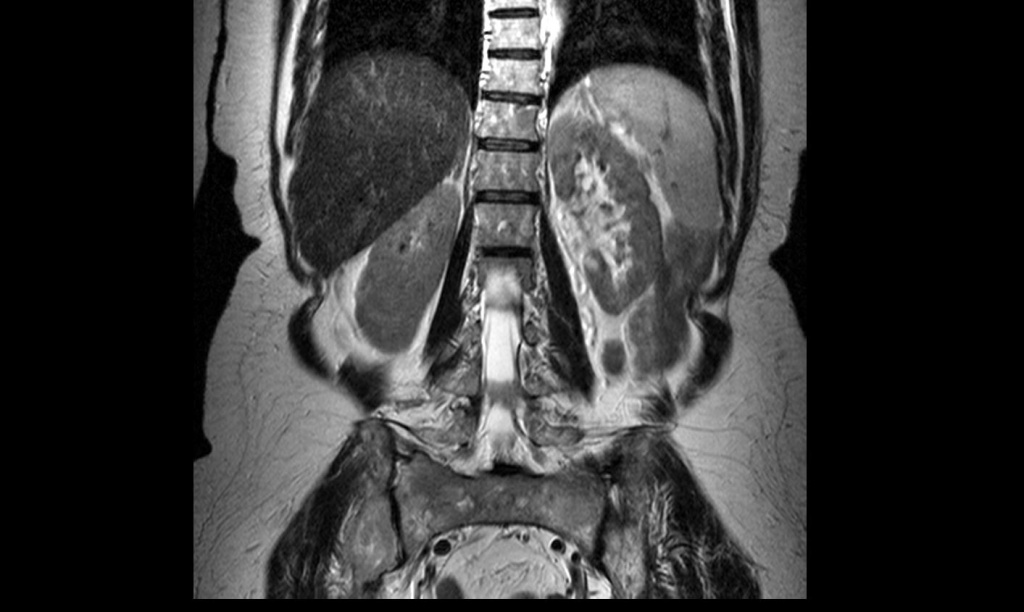

На снимке МРТ хорошо видно мышцы и костную ткань

Жалобы на боли в спине обязательно требуют диагностики. Ее проводят в несколько этапов.

- МРТ и компьютерная томография. Позволяют узнать о состоянии мягких тканей спины в области локализации боли.